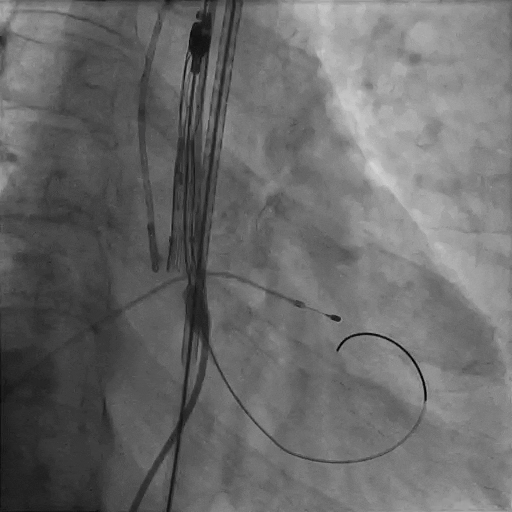

瓣膜完全释放,形态完美,无周漏